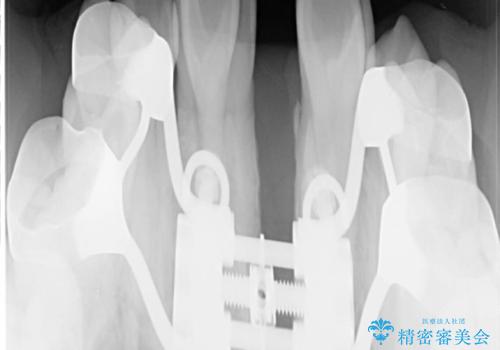

- 上顎の骨格性拡大+両側第1小臼歯抜歯 によりスペースを獲得、フルリンガルによるワイヤー矯正を計画した。